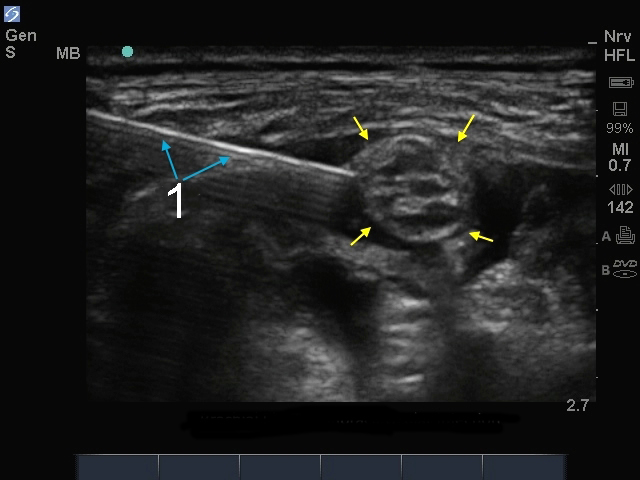

M-Turbo: Brachial Plexus Supraclavicular Injection

1. Needle

Yellow Arrows: Nerve